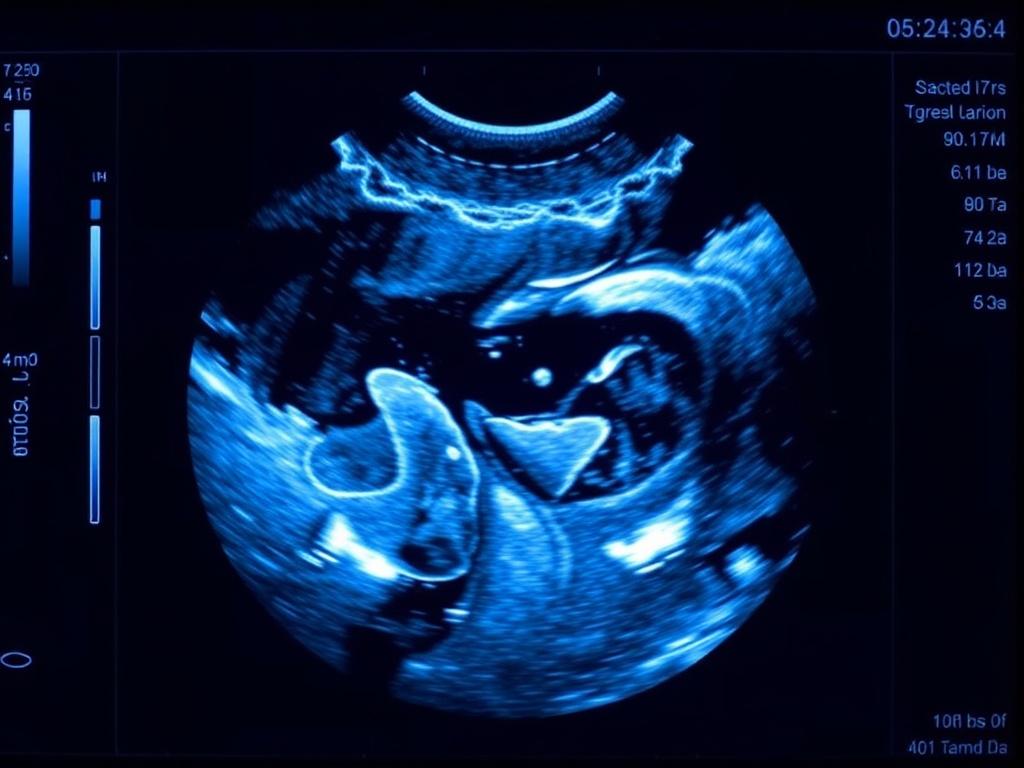

В брюшной полости ультразвук незаменим при изучении печени, желчного пузыря, поджелудочной железы и почек. Чёрно-белые изображения сопровождаются динамическими тестами: оценка двигательной активности, гепатомегалии или наличия свободной жидкости.

Кишечник сложнее для ультразвука из-за газа, но опытный сонолог может оценить толщину стенки, перистальтику и признаки воспаления. Для анатомии это важно: видеть, как петли кишечника располагаются относительно других органов в реальном времени.